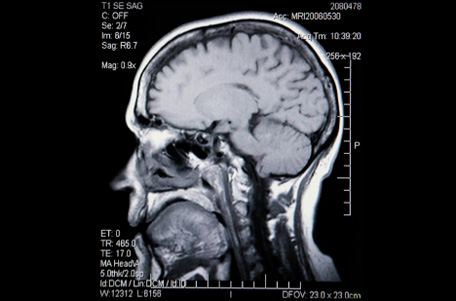

Данное обследование является комплексным профилактическим обследованием, направленным на проверку функций мозга. Оно включает в себя обследование неврологом, ЭЭГ (измерение электрической активности мозга), а также учитывает результаты МРТ черепа и лабораторных исследований.